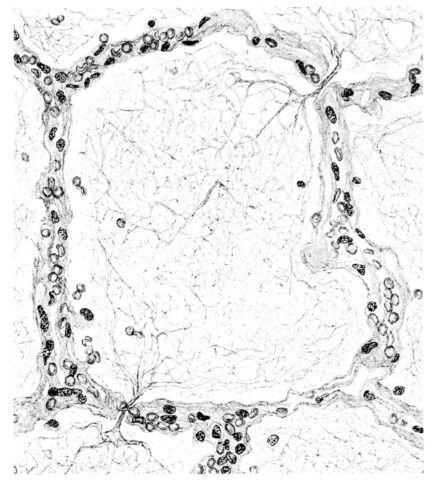

FIG. XV. AUTOPSY NO. 149. ILLUSTRATES ONE OF THE MOST STRIKING EARLY PULMONARY LESIONS; THE DILATATION OF THE TERMINAL BRONCHIOLES AND THE HYALINIZATION OF THEIR EPITHELIUM. COMPARE FIGURE XVI.

A more striking picture, however, even than this aplastic alveolar exudate appears in the terminal bronchioles. In many instances, these are conspicuous on account of their size, for they are dilated to form prominent, often irregular, sacs (Fig. XV). The distention of these terminal bronchioles may be so great that the surrounding alveoli are compressed. What makes them even more conspicuous is their lining, once epithelium, but now a swollen, thick, homogeneously staining material, with complete loss of architecture; the material forms (with hematoxylin and eosin) a red band limiting the lung tissue and sharply demarcating it from the exudate within the bronchioles (48, 92). However, this ribbon of red, often thickened by fibrin deposition, is not always pure, for bacteria thrive in the dead tissue. They occur singly, paired, in chains, and also as circumscribed, dense masses which in size and position, simulate nuclei (162) (Fig. XVI). This same hyalinization of the epithelium, it will be recalled, occurs in the larger bronchi (Fig. V), and there, too, bacteria frequently develop in the dead tissue (Fig. VIII). In the smallest bronchiolar ramifications, acute epithelial necrosis is not infrequently encountered, even when the surrounding lung tissue is relatively normal (Fig. XVI). That the process does not stop with the epithelium, but, as in the larger bronchi, may extend through the entire structure of the bronchioles, is manifest. Even the alveolar walls may be involved and frequently homogeneous pink or red bands, now the phantom of the former viable lung tissue, mark the presence of the old wall of the alveolus (Fig. XVII). Occasionally, some architecture remains in this pink ribbon and then the involvement seems to be primarily in the vessels of the wall. Not all the vessels are involved, and next to a hyaline thrombus in one, there may be fresh blood, usually red blood, in its neighbor. The alveolar epithelium is usually denuded and thus accentuates the intensity of the change.